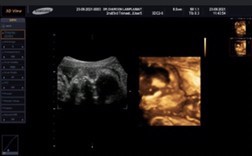

กำลังตั้งครรภ์